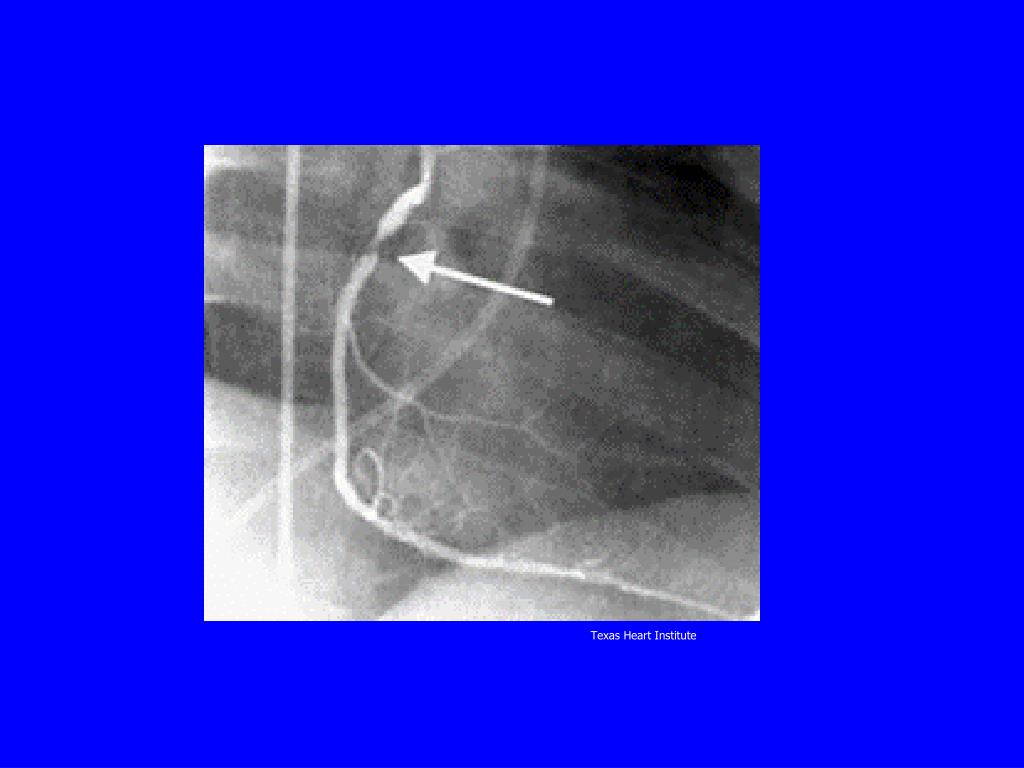

7. Texas Heart Institute